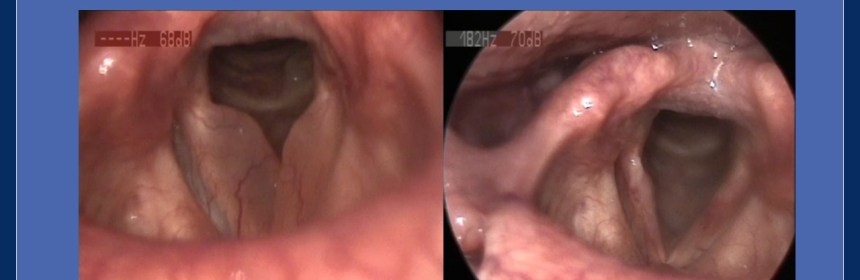

Aşağıdaki fotoğrafta cerrahi öncesi ve sonrası Reinke ödemli ses tellerinin fotoğraflarını görebilirsiniz.

Reinke Ödemi – Ameliyat öncesi ve sonrası videolaringostoboskopik muayene sırasında elde edilen fotoğraflar – Prof.Dr. Haldun Oğuz